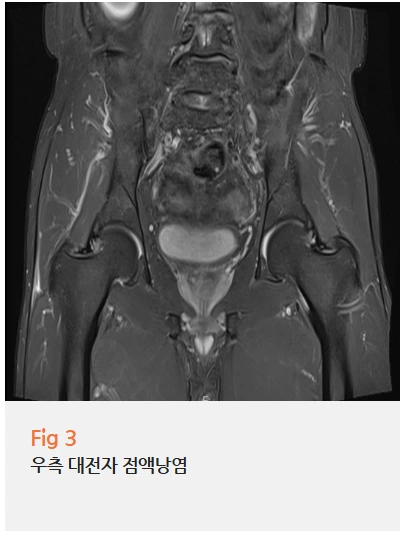

✔️ 우측 대전자 점액낭염

고관절 자체에도 문제가 있었어요.

대전자는 허벅지뼈 위쪽 바깥쪽에 튀어나온 부분인데요.

여기에 염증이 생긴 상태였어요.

주로 반복적인 마찰이나 압박으로 생기는데,

허리가 안 좋으면 보행 패턴이 틀어지면서 고관절에 무리가 가기 쉬워요.